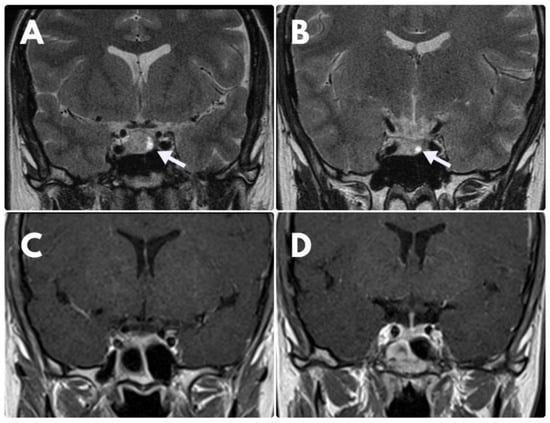

On account of lack of clinical and biochemical improvement, no regression of the tumour on MRI scans as well as DAs-resistance, the patient underwent transsphenoidal resection of the tumour in March 2019. Histological analysis revealed a sparsely granulated lactotroph adenoma with positive immunostaining for PRL and Ki-67 index >3%. In the postoperative period, CAB at the dose of 3.5 mg/week was reinstituted due to persistent hyperprolactinemia. A control MRI (February 2021) showed the complete disappearance of the initial pituitary lesion (Figure 2).

Figure 2. MRI coronal images. (A)—MRI at the time of diagnosis—visible suspicious hyperintense area at the left side of the pituitary gland (white arrow), which was diagnosed as an adenoma. (B)—control examination after 6 months of BRC treatment disclosed no significant regression of the lesion. (C,D)—control MRI after operative treatment—no visible signs of adenoma.